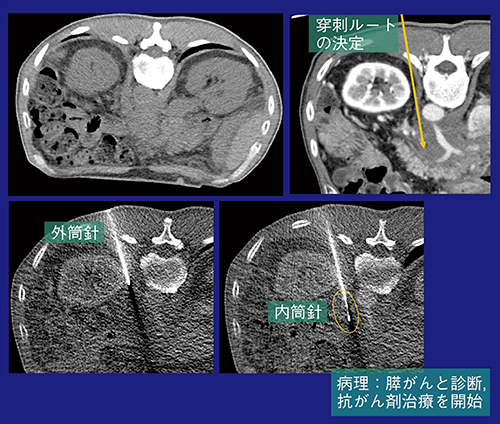

2)生検

当院におけるCT透視下での体幹部生検は,経年的に増加しており,特に2014年から,腎腫瘍に対する経皮的凍結療法を導入したことで急増している。今後も,分子標的薬導入によるバイオマーカー検査や,局所療法の適用拡大の可能性から,需要は増えることが予想される。症例3は,60歳代,男性,腹腔動脈根部に後腹膜腫瘍を認める。CA19-9も正常範囲内だが,膵がんの可能性を確認するためCT透視下生検を行った。深部腫瘍のため大血管を避けて穿刺ルートを決定する必要があり,少量の造影剤を注入し,血管走行を確認した上で穿刺針を進めることで生検を施行,膵がんと診断された(図6)。

図6 症例3:CT透視下生検